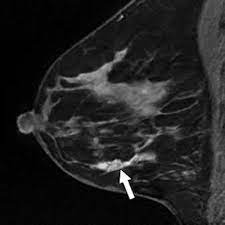

If these tests don't answer the quest. But not every woman who has been diagnosed with breast cancer needs a breast mri. Determining the extent of cancer after a new breast cancer diagnosis. It can also help detect breast cancer in women with breast implants and in younger women who tend to have dense breast tissue. An mri can be used to look for a disease, such as breast cancer. But there are also other reasons to have a breast mri. Inflammatory breast cancer affects breast tissue and can appear unusually dimpled or thick. Breast mri images are combined, using a computer, to create detailed pictures. A waiver of informed consent Mri scan is also used in breast screening for young women who are at higher risk of developing cancer. Dcis on mri may create an area of irregular enhancement of the mri dye into the breast. They're often easy to move around (mobile) and may be tender. A breast mri is a highly effective test.

Lobular breast cancer can be more difficult to see on imaging and scans. Recent research has found that mri can locate some small breast lesions sometimes missed by mammography. Your doctor may recommend a breast mri for the following: The dye collection in the breast can also look clumpy or appear in a section of the breast, depending on the involvement of dcis. Some benign conditions such as fibrocystic disease can look like cancer.

The Radiology Assistant Mri Of The Breast from radiologyassistant.nl Your doctor may recommend a breast mri for the following: A breast mri captures multiple images of your breast. This is why we ask questions about menstrual cycle and hormone therapies prior to your study. What does breast cancer look like on a mammogram? Dcis on mri may create an area of irregular enhancement of the mri dye into the breast. The features of a malignant breast condition on mri scan are often to do with the outer irregular borders of a lesion. An mri can be used to look for a disease, such as breast cancer. If you are at risk of getting a certain disease, your caregiver may want to do an mri to look for signs of the disease.

An mri can help find a disease of the lungs or show tumors (growths) in the chest. But not every woman who has been diagnosed with breast cancer needs a breast mri. The features of a malignant breast condition on mri scan are often to do with the outer irregular borders of a lesion. A rash isn't the only visual symptom of inflammatory breast cancer. Any area that does not look like normal tissue is a possible cause for concern. A breast mri scan might also be used to assess the size of the cancer to check which kind of surgery is possible. They work to destroy the tumor or slow down the growth of cancer cells. This appears most commonly as streaking, known as linear enhancement. On the flip side, there are benign (not cancerous) breast changes which can mimic breast cancer as well. This means that the test finds a mass or other change that seems to show cancer but it is not cancer. Breast mri images are combined, using a computer, to create detailed pictures. What does breast cancer look like on a mammogram? The dye collection in the breast can also look clumpy or appear in a section of the breast, depending on the involvement of dcis.